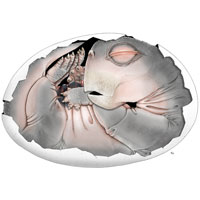

Это самое известное фото возбудителя скарлатины Streptococcus pyogenes, оно сделано еще в 1979 году через световой микроскоп с увеличением в 900 раз. Изображение получилось очень художественным и необычным — аккуратные цепочки микроорганизмов словно складываются в буквы. Конечно, обычно картина в окуляре микроскопа далеко не такая красивая. Чтобы бактерию было хорошо видно, образец человеческого гноя из носоглотки окрасили по методу Паппенгейма. Заключается этот метод в том, что сперва наносят краску Май-Грюнвальда, которая окрашивает форменные элементы крови (серо-зеленые сгустки на фото — это цитоплазма лимфоцитов), затем ее смывают и добавляют раствор краски Романовского-Гимза — он окрашивает бактерии в фиолетово-красный цвет. Метод Паппенгейма появился еще в начале прошлого века, а этот образец сфотографировали почти 40 лет назад при не самом лучшем освещении — видимо, так можно объяснить желтоватый оттенок снимка и оранжевые бактерии вместо фиолетово-красных. Тем не менее этот метод до сих пор используют для окраски стрептококков — во многом для создания демонстрационных материалов и обучения студентов, ведь заболевания, вызываемые бактериями этого рода, диагностируют не при помощи микроскопии, а по клинической картине.

Фото с сайта phil.cdc.gov.

Так выглядит современная фотография мазка, содержащего Streptococcus pyogenes, при окрашивании методом Паппенгейма. Фото с сайта sciencesource.com